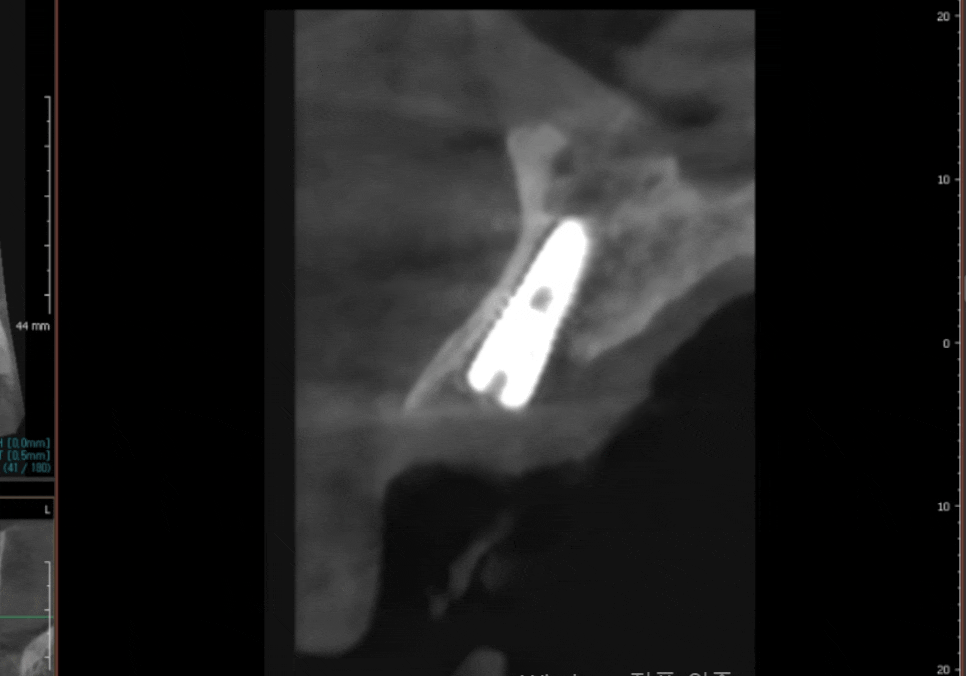

정확한 원인을 파악하기 위해

디지털 파노라마와 CT 데이터를

면밀히 분석한 결과,

결과는 생각보다 훨씬 안타까웠습니다.

#12 치아는 만성 치주염으로 인해

이미 뿌리 끝까지 잇몸뼈가

녹아버린 상태였어요.

CT상에서도 뿌리 끝 아주 일부분만

겨우 뼈에 걸쳐져 있는게 보이시나요?

250424

아쉽지만, 아무리 좋은 크라운을 씌운다 해도

치아를 살릴 수 있는 '골든타임'을

이미 놓친 상황이었죠ㅜㅜ

반면, 바로 옆의 #22 치아는 충치는 깊었지만

뿌리를 잡아주는 뼈가 튼튼했기에

충분히 살려서 크라운으로

치료할 수 있다는 판단이 섰습니다.